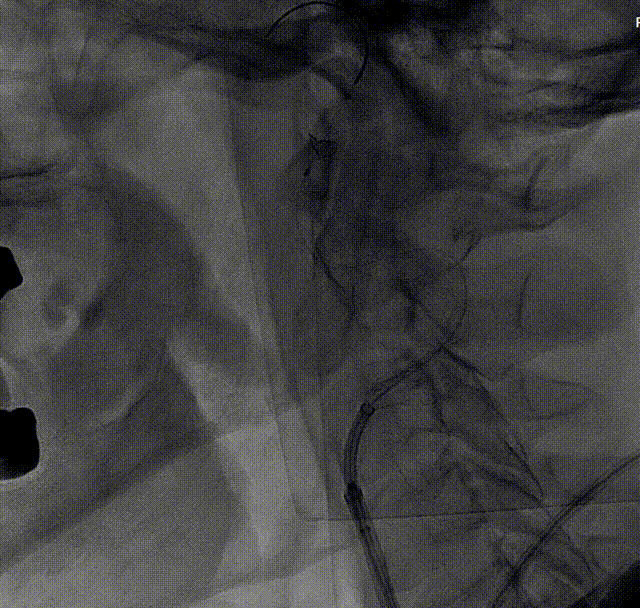

将中间导管撤至颈总动脉,通过Workhorse导丝送入4mm*20mm球囊至右侧颈内动脉狭窄病变处,准确定位后以适当压力预扩狭窄病变,造影示狭窄改善不明显。撤出球囊,再次通过Workhorse导丝送入5mm*30mm球囊至狭窄病变处进行扩张,造影提示狭窄稍改善。